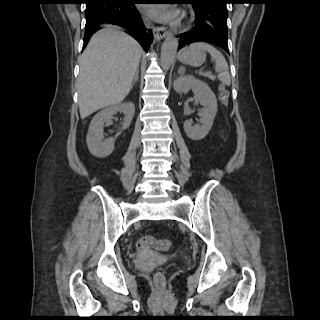

A CT abdomen revealed a left adrenal cortical tumor.

Her abdominal X-ray also reveals a right renal stone although she never complained of renal colic.

CT images: